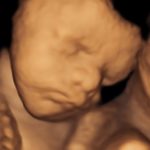

4D/5D/HD Ultrasound Gallery

Gallery